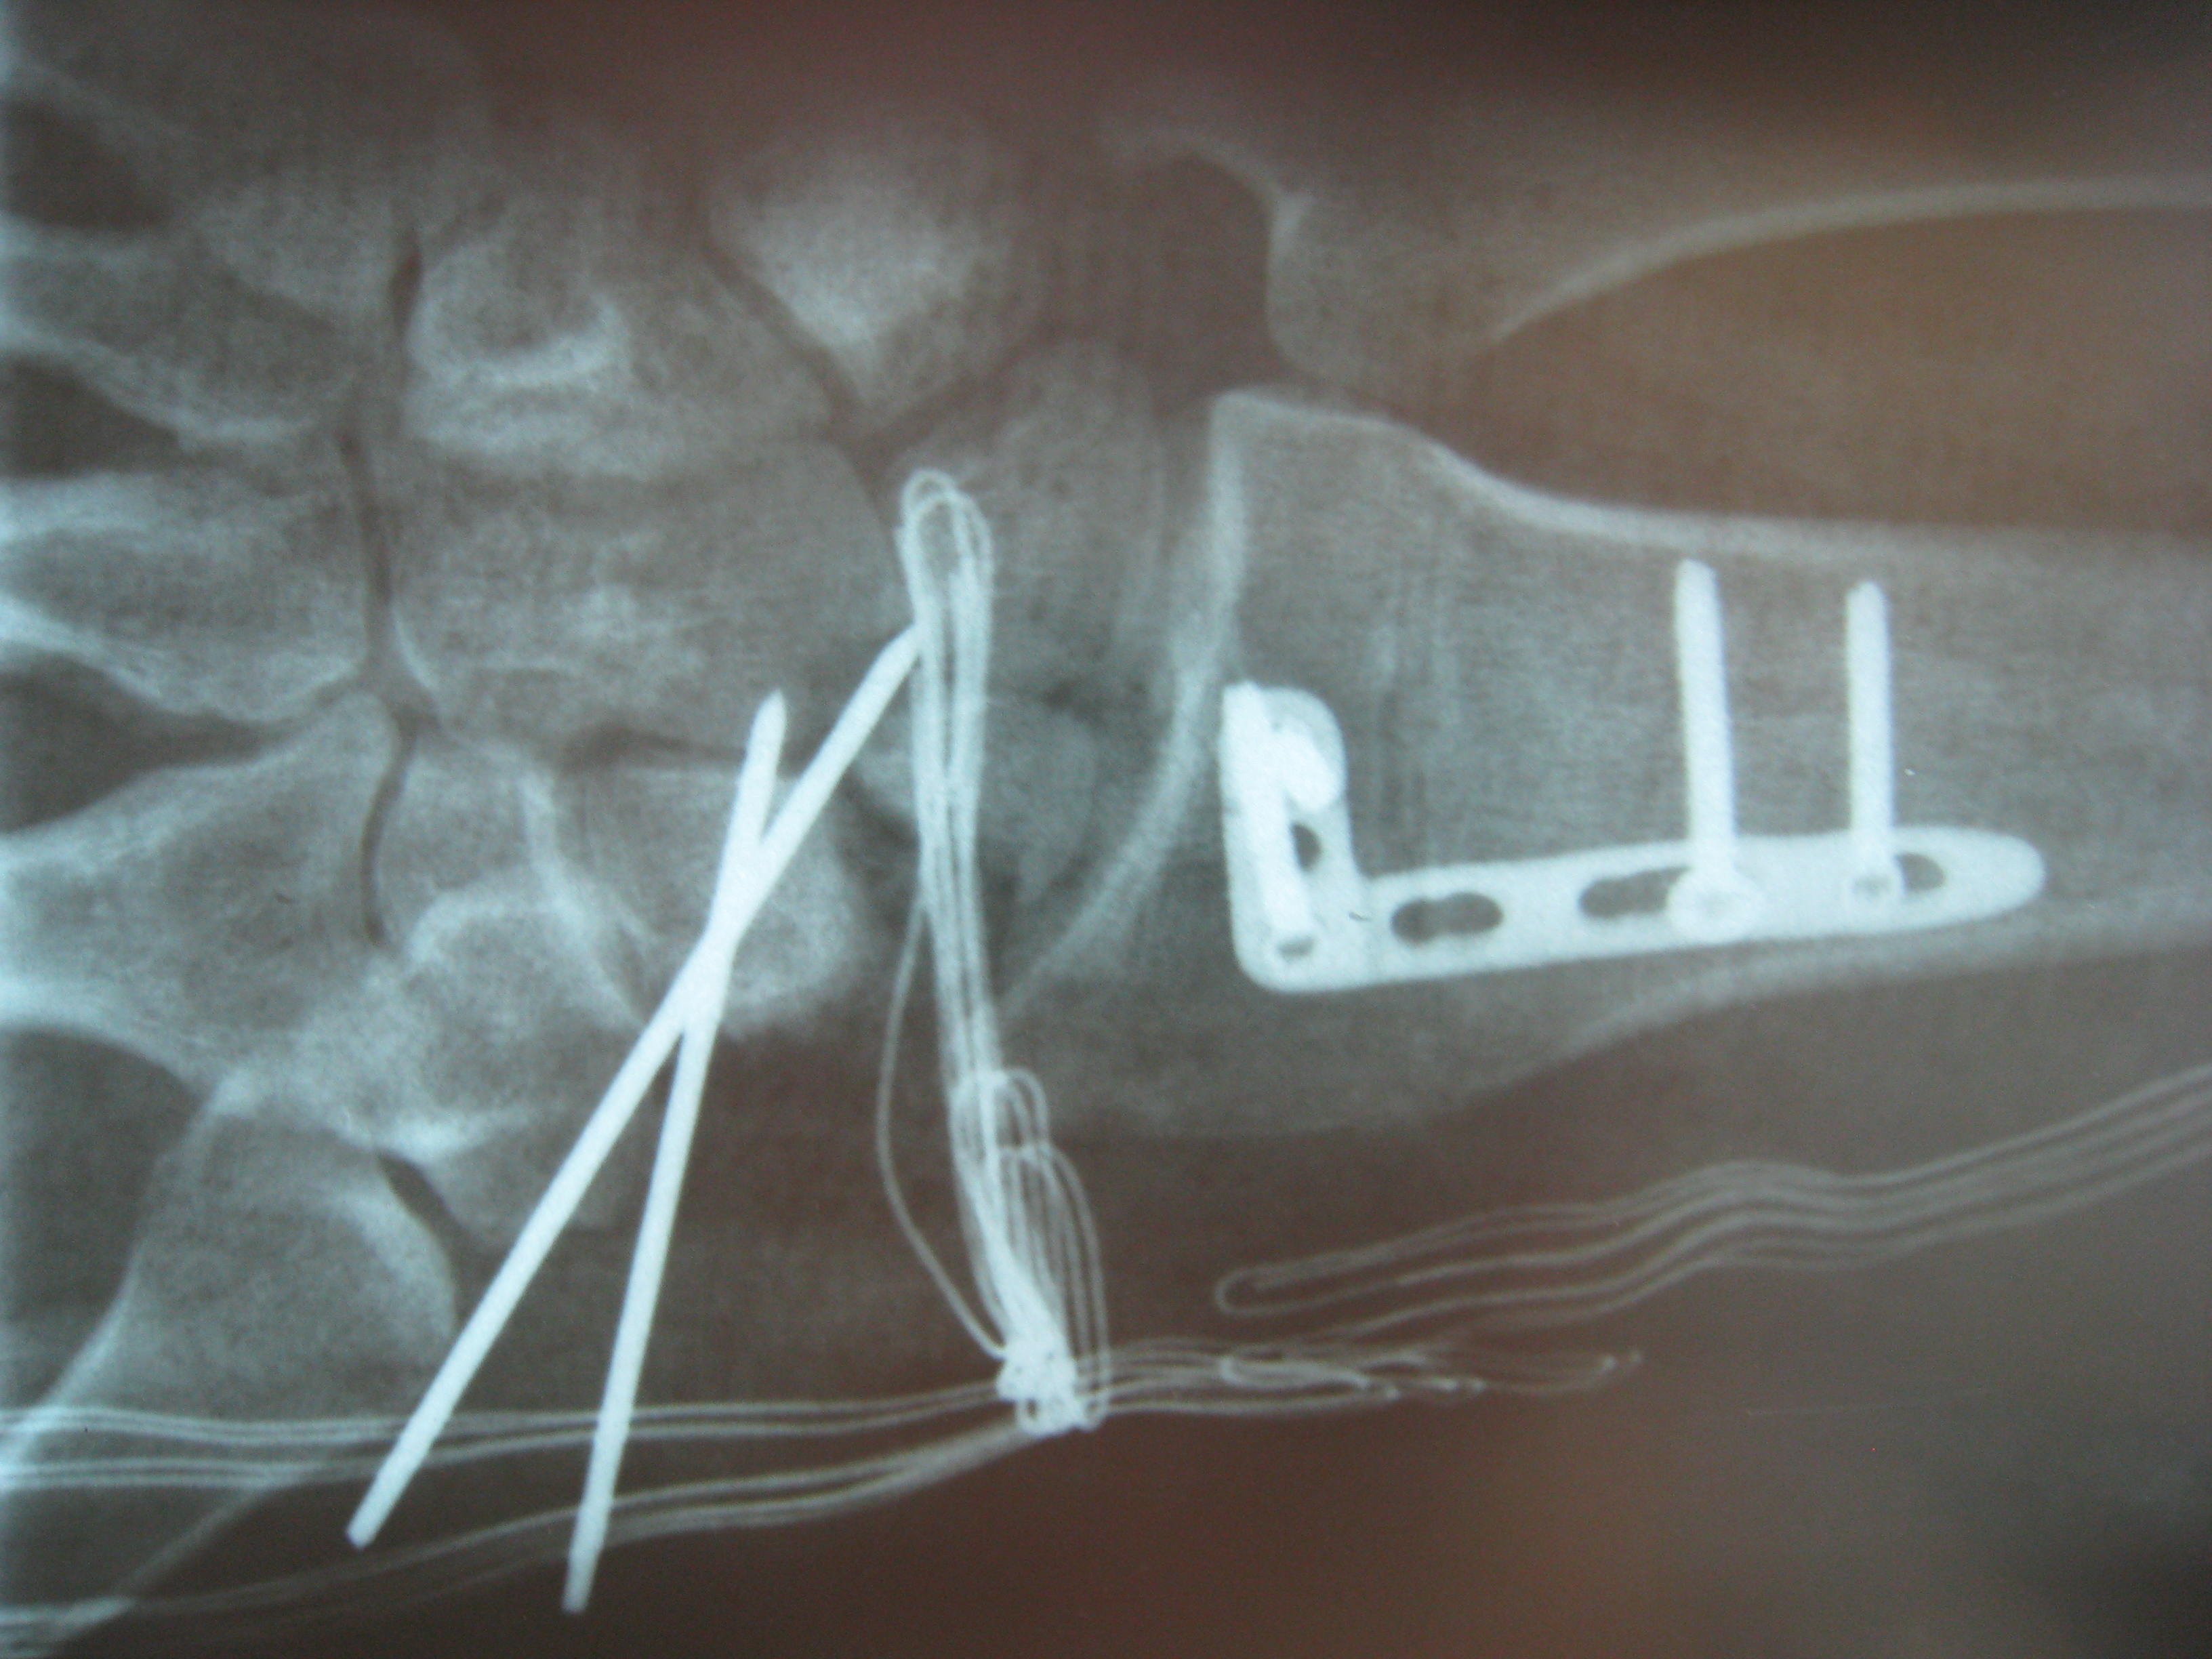

Η αντιμετώπιση της ψευδάρθρωσης του σκαφοειδούς είναι πάντοτε χειρουργική. Με ραχιαία ή παλαμιαία προσπέλαση αποκαθίσταται ο άξονας του σκαφοειδούς και σταθεροποιείται το σκαφοειδές με ειδική βίδα ή βελόνες, με παράλληλη τοποθέτηση οστικών μοσχευμάτων. Μπορεί επιπλέον να γίνει και οστεοτομία κλειστής σφήνας του περιφερικού άκρου της κερκίδος. Στις περιπτώσεις άσηπτης νέκρωσης το μόσχευμα πρέπει να είναι αγγειούμενο – για να προσδώσει αιμάτωση στο νεκρωμένο κεντρικό τμήμα – και λαμβάνεται με μικροχειρουργικές τεχνικές από το περιφερικό τμήμα της κερκίδος ή από άλλα τμήματα του σώματος

Μετεγχειρητικά 2

Περίπτωση 2: Μετεγχειρητικά 2